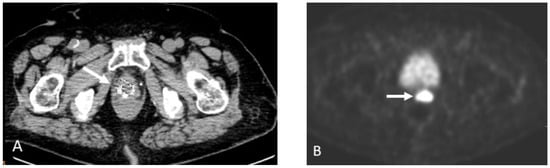

Detection of Loco-Regional Disease and Distant Metastases